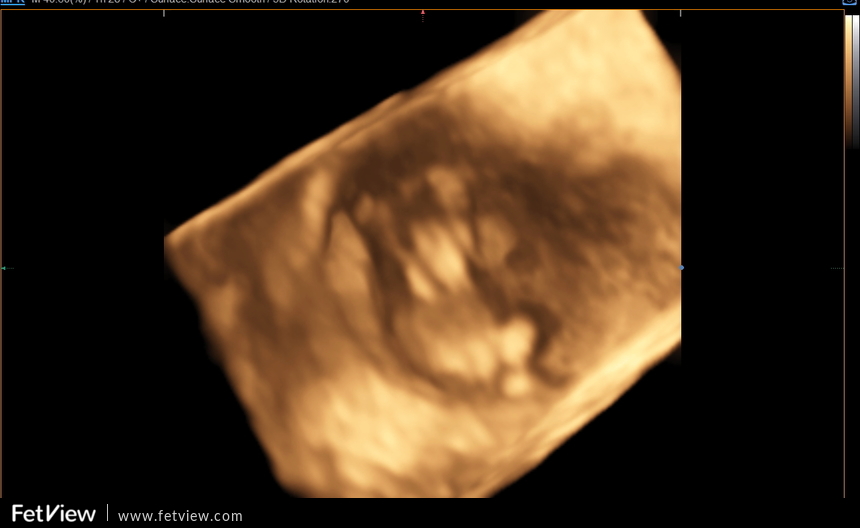

3D ultrazvuk. Co mi to pan doktor vlastně vyfotil?

@martiniquest Díky moc, já tam totiž nic nevidím :D Bylo to poprvé přes břicho a ani nevím, proč mi pan doktor fotil 3D =)

@kate4597 To taky moc nechapu, protoze tohle je jeste velmi nizky stupen tehotenstvi a jsou to takovi mali mimozemstani 😆

Vidim tam cely plod. Vypada jak male prasatko (bez urazky, jen pro ilustraci, at vidíš to same), ma jeste kratke koncetiny